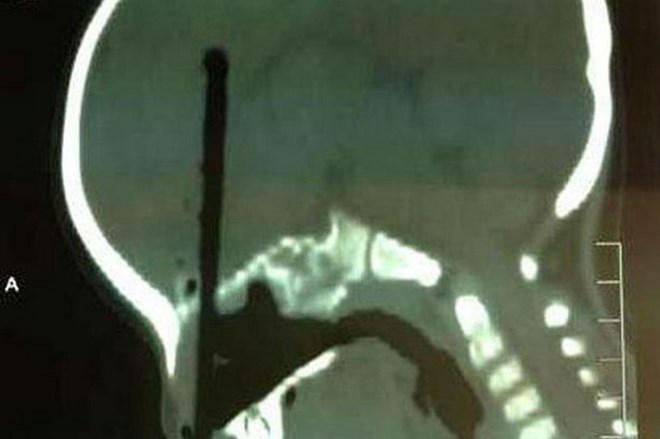

Các bác sĩ phải mất 4 tiếng phẫu thuật để lấy chiếc đũa raSau 4 tiếng đồng hồ phẫu thuật căng thẳng, các bác sỹ cuối cùng cũng lấy ra được chiếc đũa đã đâm sâu hơn 7 cm vào não cậu bé có tên Huang Zicheng.

Rất may là cái đũa không gây ra tổn thương nghiêm trọng nào cho tế bào não hay động mạch. Cậu bé được hy vọng sẽ hồi phục hoàn toàn.

Cha của cậu bé cho biết mình phát hiện ra tai nạn khi nghe thấy Zicheng hét lên. "Tôi quay lại và kinh hoàng nhìn thấy chiếc đũa đã cắm sâu vào mũi thằng bé," người cha cho biết.